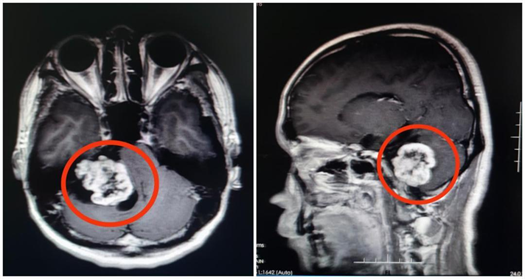

“从影像资料来看,怀疑是听神经瘤的可能性比较大。”该院副院长鲁明接诊时,发现一个鸡蛋大小的肿瘤正压着患者的内听道和脑干。除肢体乏力、面肌痉挛、头痛等症状外,还严重影响了他的听力。

完善术前准备,鲁明教授带领神经外五科团队为刘超行右侧桥小脑角占位性病变切除术,全切肿瘤。术后病理结果证实为听神经瘤。